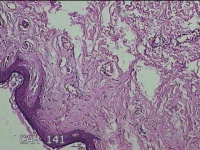

右后颈部包块

性别

女

年龄

31岁

临床诊断

头颈皮脂腺囊肿

一般病史

发现后颈部包块1年余。

标本名称

大体所见

灰白粉红色包块2.3x1.5x0.8cm一个,表面光滑,带少许脂肪,部分已切开,切面灰白粉红色,质中。